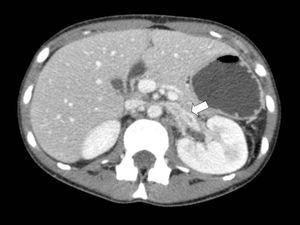

Se practicó una angio-tomografía computarizada, que ya no demostró la presencia de trombosis de la vena cava inferior, pero sí trombosis de la vena renal y la vena ovárica izquierda (figura 1), así como una estenosis de la vena renal izquierda en su paso entre la aorta y la arteria mesentérica superior, compatible con un SCN (figura 2).

Figura 1. Trombosis de la vena renal izquierda y compresión de esta durante su paso entre la aorta y la mesentérica superior compatible con síndrome del cascanueces.